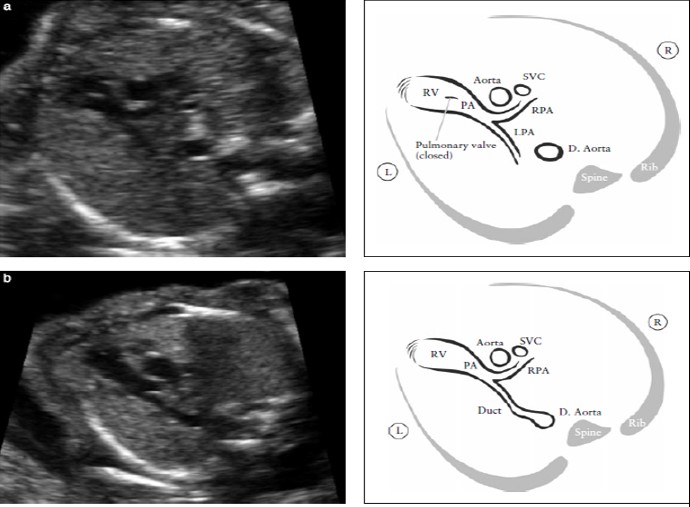

Проекция выходного тракта правого желудочка подтверждает выход магистрального сосуда (легочной артерии) из морфологически правого желудочка (Рисунок 6). В норме легочная артерия выходит из правого желудочка и направляется влево и несколько кпереди от восходящей аорты.

Как правило, во время внутриутробной жизни плода, легочная артерия немного больше по размерам, чем аорта и пересекает восходящую аорту почти под прямым углом чуть выше места ее выхода. В этой плоскости, как показано на рисунке 6, верхнюю полую вену часто можно увидеть справа от аорты.

Рисунок 6. Выходной тракт правого желудочка. Этот срез демонстрирует соединение между сосудом и правым желудочком. (RV). В нормальном сердце этот сосуд пересекает аорту, что помогает идентифицировать его как легочную артерию (PA). Клапан легочной артерии не должен быть утолщен и должен свободно открываться. Рисунок (а) демонстрирует бифуркацию легочной артерии на две ее ветви. Легочный клапан закрыт.

Рисунок (b) демонстрирует срез при продвижении датчика в сторону головки плода. На нем видны: PA- легочная артерия, RPA- правая ветвь легочной артерии и артериальный проток. D. Aorta- нисходящая аорта, L- левый, LPA- левая ветвь легочной артерии, R- правый, SVC- верхняя полая вена.

Эта проекция представляет собой срез через три сосуда, описанный Yoo et al [64]. Клапан легочной артерии должен двигаться свободно и не иметь уплотнений. Если сосуд, отходящий от правого желудочка, почти сразу разветвляется (бифуркация), значит это – легочная артерия.

Сначала отходит правая ветвь легочной артерии, а затем отходит и левая ветвь. Из-за положения плода это разделение не всегда можно увидеть. В норме, легочная артерия продолжается дистально по левой стороне вплоть до артериального протока, который потом соединяется с нисходящей аортой (Рисунок 6 и Приложение S1).